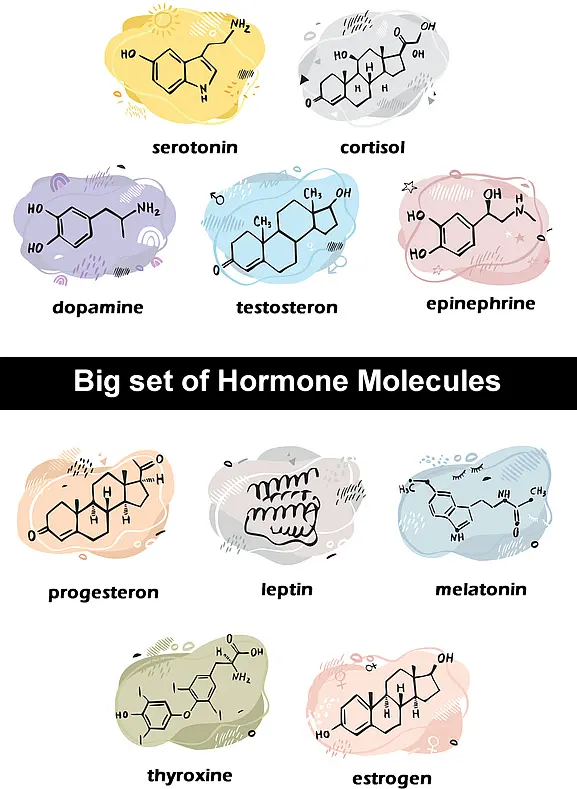

Hormones

There are many hormones which can cause Acne. Many of these hormones are linked to puberty, and can change how the skin develops and responds to hormones. Some other factors that can contribute to Acne include genetics, diet, and lifestyle. Follow up with Naturopathic Doctors in regards to Female Hormone Panel and Male Hormone Panel. Acne hormones e.g., Serotonin, Cortisol, Dopamine, Testosterones, Epinephrine, Progesteron, Leptin, Metalonin, thyroxine, and Estrogen seems to play a role in the development of acne, and they may also be responsible for the severity of acne. In addition, it appears that different acne hormones work together to cause the condition.

Naturopaths are a growing and popular form of alternative medicine. We at Grimsby Acne Clinic often prescribe natural care for common ailments, such as hormone acne. Naturopaths may recommend supplements or natural medications to regulate hormones, which can help reduce the severity and frequency of acne breakouts.